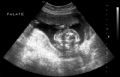

Normal cervical spine at 18 weeks (1). Another normal sagittal view of cervical spine seen in third trimester with folds of fat seen (2). Normal thoracic spine at 18 weeks (3). Normal sagittal view of lumbosacral spine at 18 weeks (4). Normal transverse view of lumbosacral spine at 18 weeks (5). - Extremities (hands/feet)